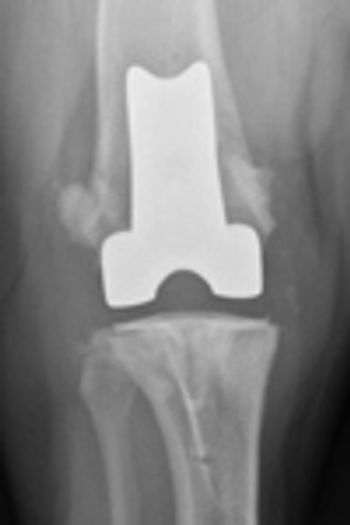

Metallic implants placed in the body should be corrosion-resistant, biocompatible, and must have adequate strength to withstand functional stress. Corrosion of metal occurs because of the electrochemical ions in body fluid. Most metal implants currently used in veterinary surgery are of 316L stainless steel.